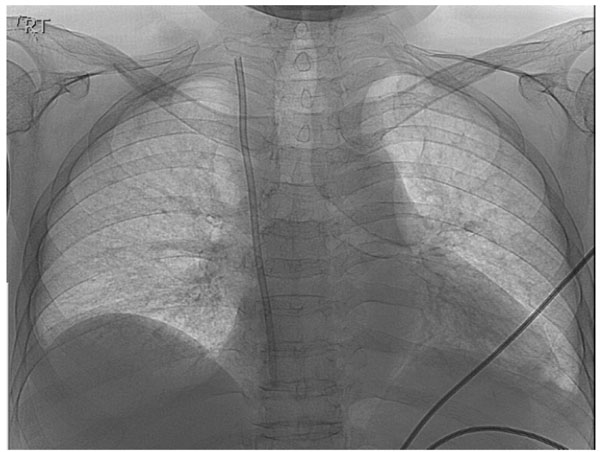

Fig. (1)

The proximal segment of the BIO-FLEX

®

TESIO

CATH seen in the superior vena cava and the right atrium.